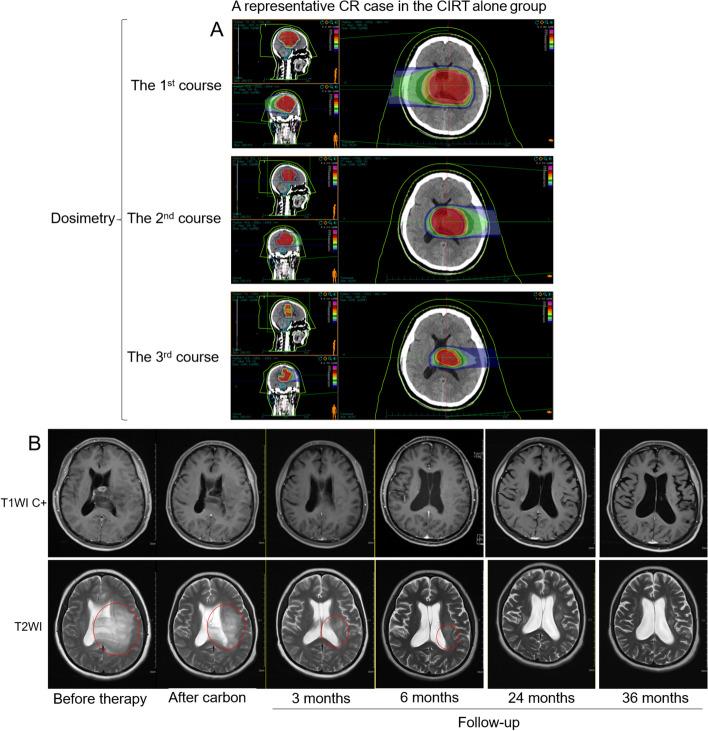

This study aimed to compare the survival outcome and side effects in patients with primary high-grade glioma (HGG) who received carbon ion radiotherapy (CIRT) alone or as a boost strategy after photon radiation (photon + CIRT).

Thirty-four (34) patients with histologically confirmed HGG and received CIRT alone or Photon + CIRT with concurrent temozolomide between 2020.03-2023.08 in Wuwei Cancer Hospital & Institute, China were retrospectively reviewed. Overall survival (OS), progression-free survival (PFS), and acute and late toxicities were analyzed and compared.

Eight WHO grade 3 and 26 grade 4 patients were included in the analysis. The median PFS in the CIRT alone and Photon + CIRT groups were 15 and 19 months respectively for all HGG cases, and 15 and 17.5 months respectively for grade 4 cases. The median OS in the CIRT alone and Photon + CIRT groups were 28 and 31 months respectively for all HGG cases, and 21 and 19 months respectively for grade 4 cases. No significant difference in these survival outcomes was observed between the CIRT alone and Photon + CIRT groups. Only grade 1 acute toxicities were observed in CIRT alone and Photon + CIRT groups. CIRT alone group had a significantly lower ratio of acute toxicities compared to Photon + CIRT (3/18 vs. 9/16, p = 0.03). No significant difference in late toxicities was observed.

Both CIRT alone and Photon + CIRT with concurrent temozolomide are safe, without significant differences in PFS and OS in HGG patients. It is meaningful to explore whether dose escalation of CIRT might improve survival outcomes of HGG patients in future randomized trials.